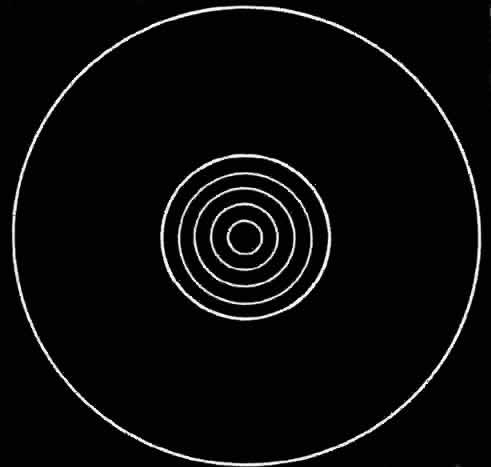

Fig 4. Representation of image of annuli of keratoscope target as formed by central

portion of cornea which is free of astigmatism. Fig 4. Representation of image of annuli of keratoscope target as formed by central

portion of cornea which is free of astigmatism.

|